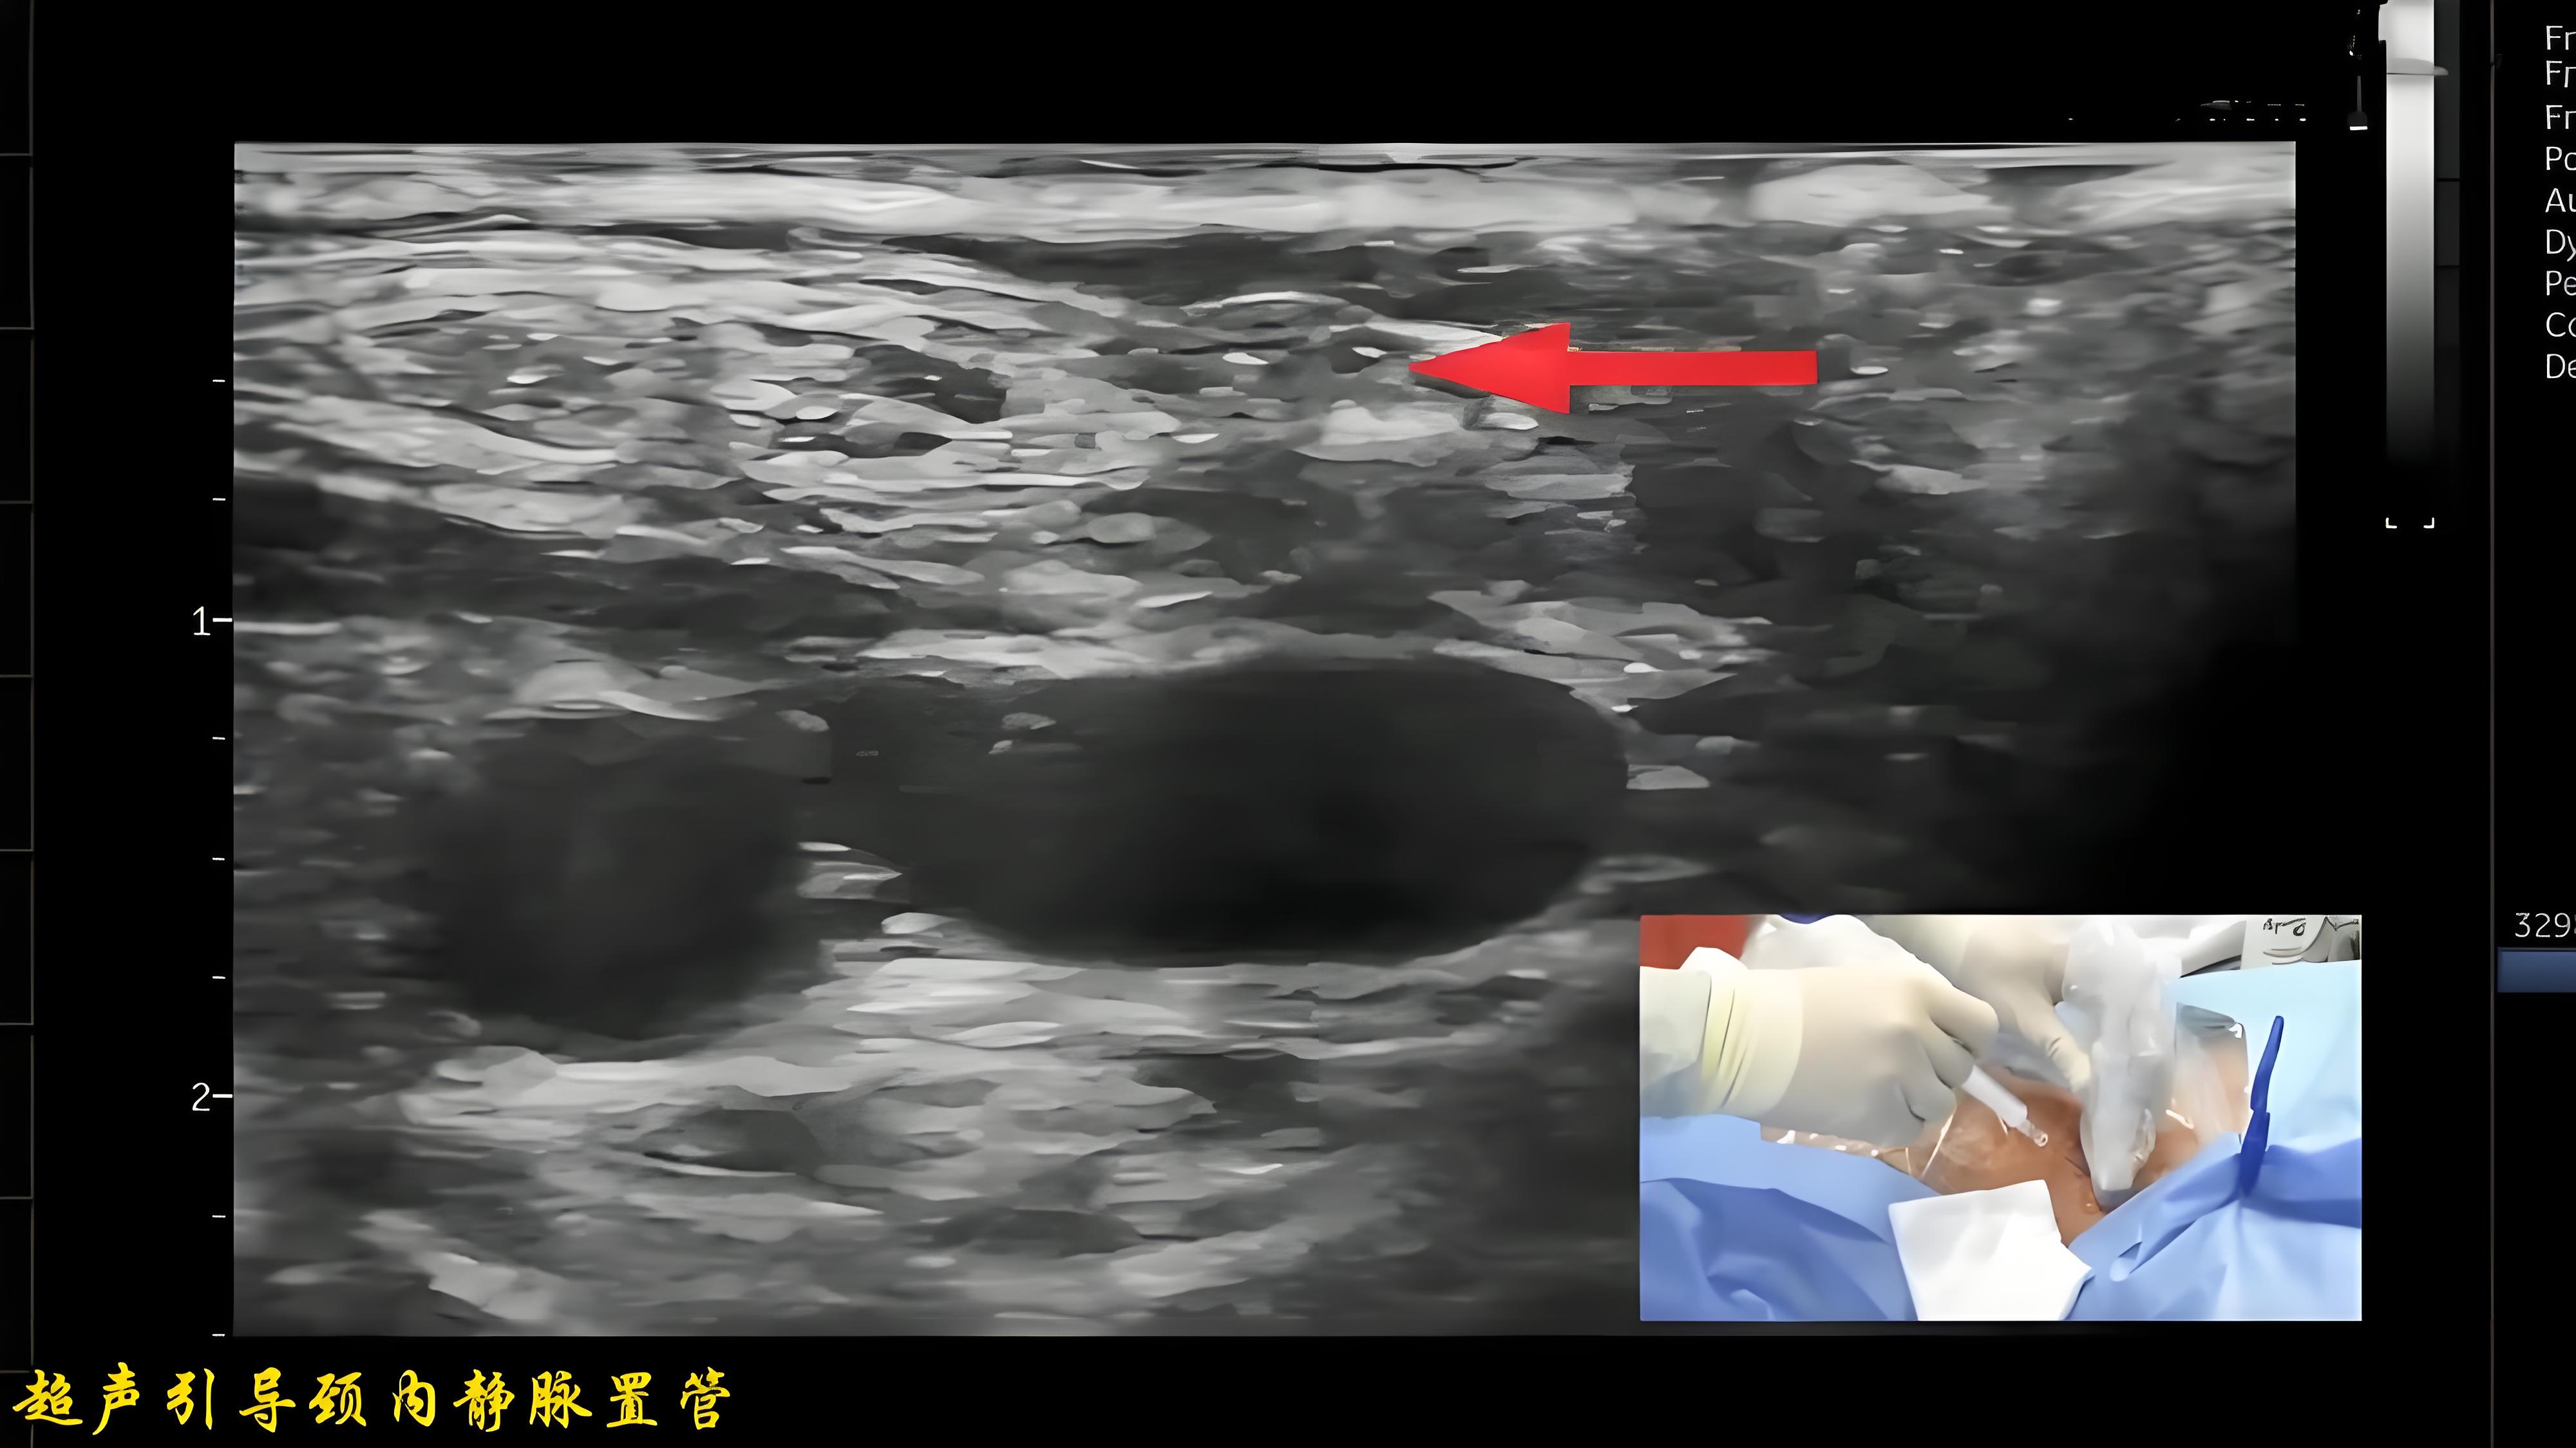

超声实时引导下颈内静脉穿刺置管

135 #颈内静脉穿刺